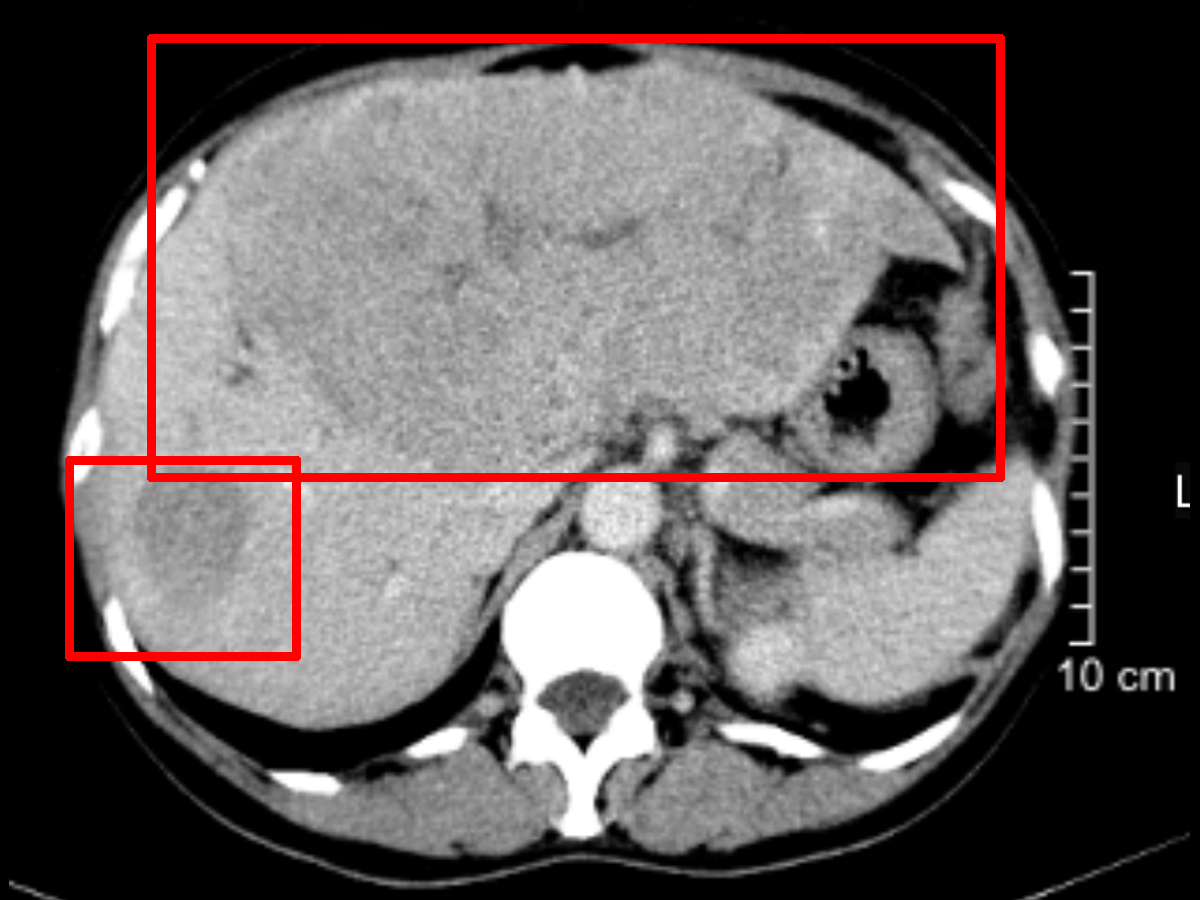

馮大爺近期總感覺右上腹隱痛不適,由于工作繁忙,檢查拖后了一段時(shí)間,等前往當(dāng)?shù)蒯t(yī)院檢查時(shí),當(dāng)?shù)氐腃T檢查結(jié)果提示該患者肝臟有巨大陰影,患者得知結(jié)果后較為擔(dān)心,認(rèn)為有誤診的可能,于是來我院就診。經(jīng)過詢問患者的基本情況后,建議患者進(jìn)行乙肝兩對(duì)半檢查、肝功能檢查、肝膽MR平掃加增強(qiáng)CT、甲胎蛋白等檢查,結(jié)果發(fā)現(xiàn)該患者的甲胎蛋白>6萬,腫瘤體積巨大,已達(dá)到15cm,并且瘤體侵犯主要血管,初診考慮為原發(fā)性巨塊型肝癌、門脈癌栓,但仍需要進(jìn)一步詳細(xì)檢查,以查看是否有肺轉(zhuǎn)移、骨轉(zhuǎn)移的可能。

肝惡性腫瘤01.jpg